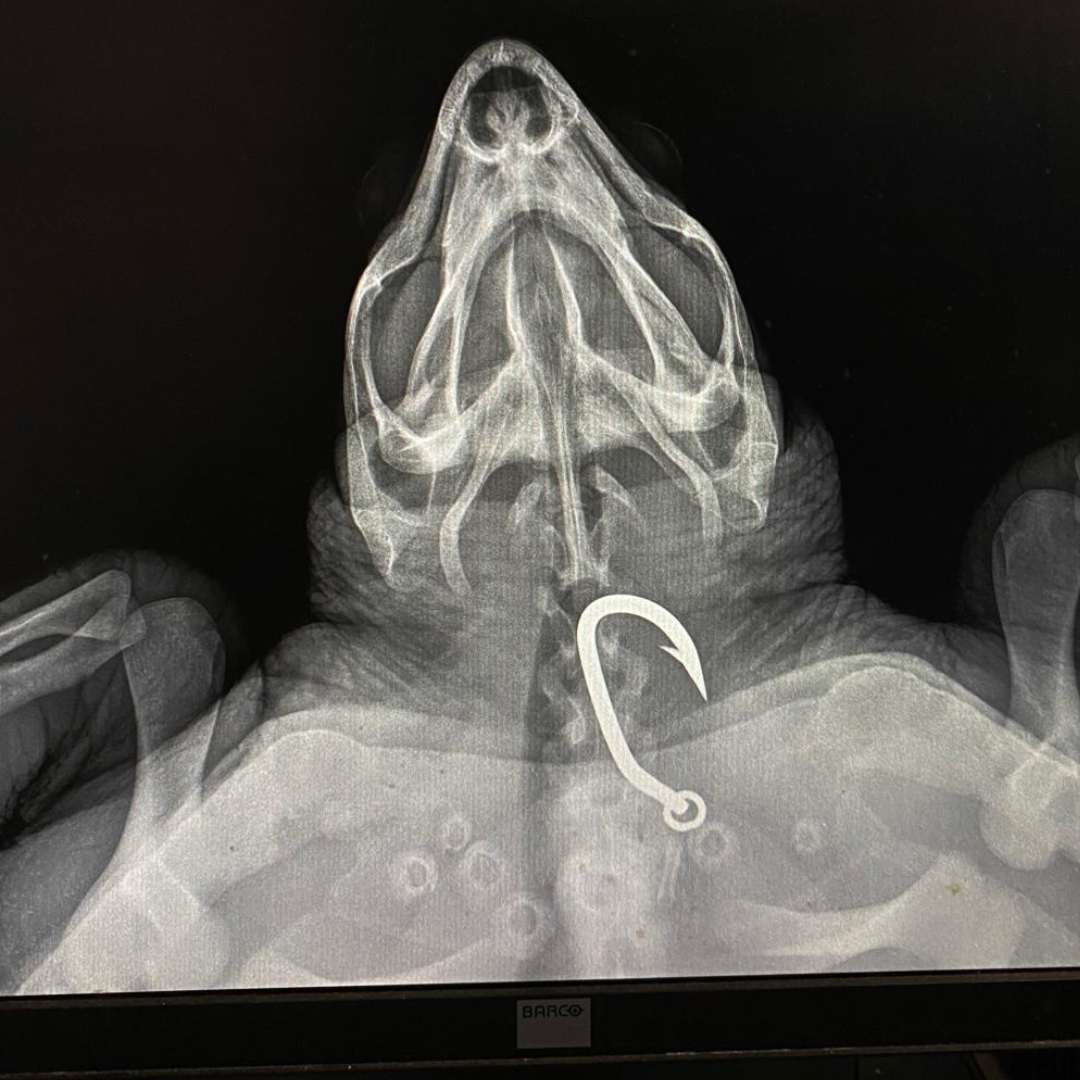

Ωστόσο, δεν ήταν όλες οι συναντήσεις συνηθισμένες. Την 1η Αυγούστου, η ομάδα βρήκε μια χελώνα Καρέττα ακίνητη στον βυθό. Χάρη στην άμεση αντίδρασή τους, η χελώνα, που ονομάστηκε «Μπριός», διασώθηκε και μεταφέρθηκε στο λιμάνι της Κόπραινας και στη συνέχεια στο Κέντρο Διάσωσης του ΑΡΧΕΛΩΝ στη Γλυφάδα. Η ακτινογραφία αποκάλυψε ότι είχε καταπιεί ένα μεγάλο αγκίστρι. Η διάσωσή της αναδεικνύει τις διαρκείς απειλές που αντιμετωπίζουν οι θαλάσσιες χελώνες και την κρίσιμη σημασία ενός δικτύου διάσωσης.